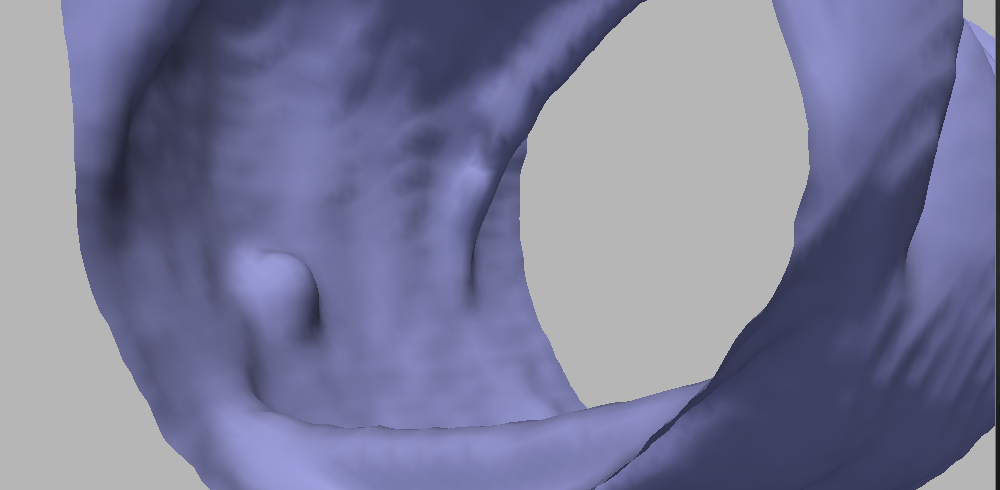

A classical motion that appears to be well suited for our problem is the motion by minimal curvature [45]. Indeed, polyps have a curve of inflection points all around it, separating its upper and lower sections (see Figure 6). Along this curve, the minimal curvature is , and therefore this section of the polyp does not move (or moves very slowly), so intuitively under this motion the polyps should persist longer. In our application, this evolution yields very good results in terms of both surface smoothing and polyp enhancement.

This PDE can be modified to obtain better results in terms of polyp detection. We now propose a set of modifications that lead us to the proposed smoothing evolution equation, and we show qualitative results to support this claim. The improvement in terms of polyp detection performance is discussed in Section V.

The first modification is inspired by the exponent of the affine motions in dimension , and yields to the following curvature motion equation:

Figure 7 shows the result after a few iterations; comparing to Figure 5, it can be readily seen that this motion achieves a better trade-off in terms of noise reduction and polyp preservation. Figure 8 evidences the difference with a comparative image: the result of the motions by and are shown in gray and in orange, respectively. On the polyp protrusion, the orange surface is above the gray surface, while the opposite is observed in the surrounding area. This shows that the evolution by leads to better polyp enhancement.